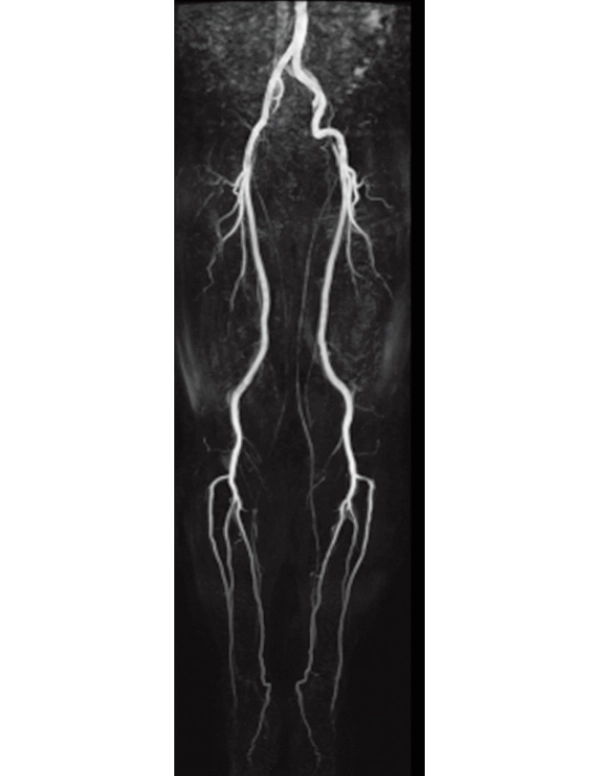

3D MRCPA (MIP)

Lower extremity

non-contrast MRA (MIP)